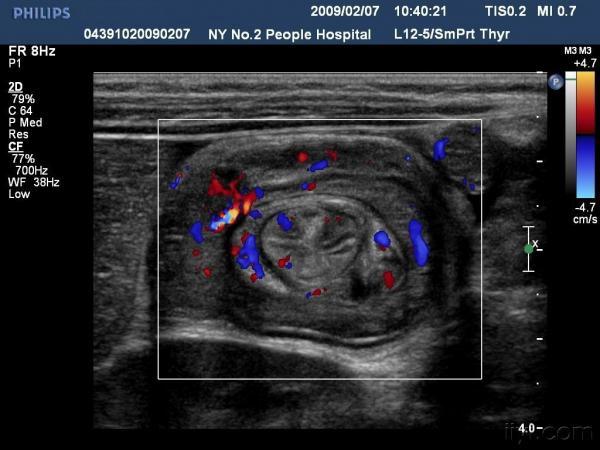

【贴图】肠套叠

患儿哭闹数小时来我院就诊,超声检查发现右侧相当于结肠肝区位置可见“同心圆征”。来和大家分享一下,呵呵。